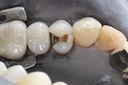

Alan Chinn #2 & 5 pre-op